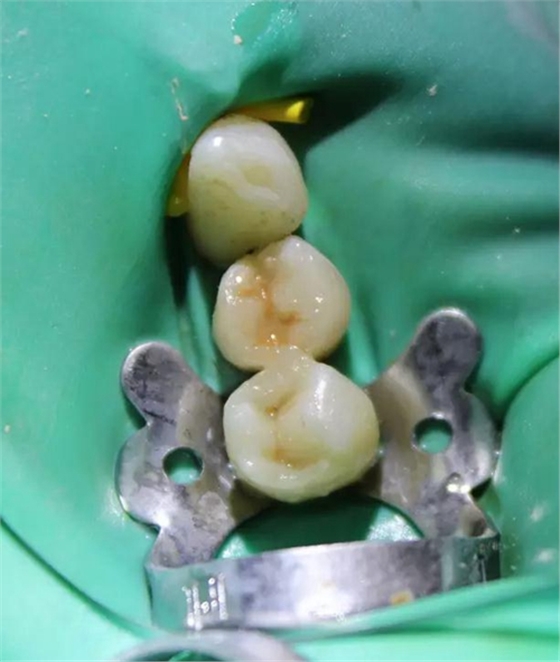

圖3 核修復(fù)完畢(橡皮障未去除)。這種2層堆疊技術(shù)非常快速,且調(diào)(牙合)更少。

圖6 左下4和左下5使用瓷納美通用修復(fù)型樹脂及SDR修復(fù)后的效果。